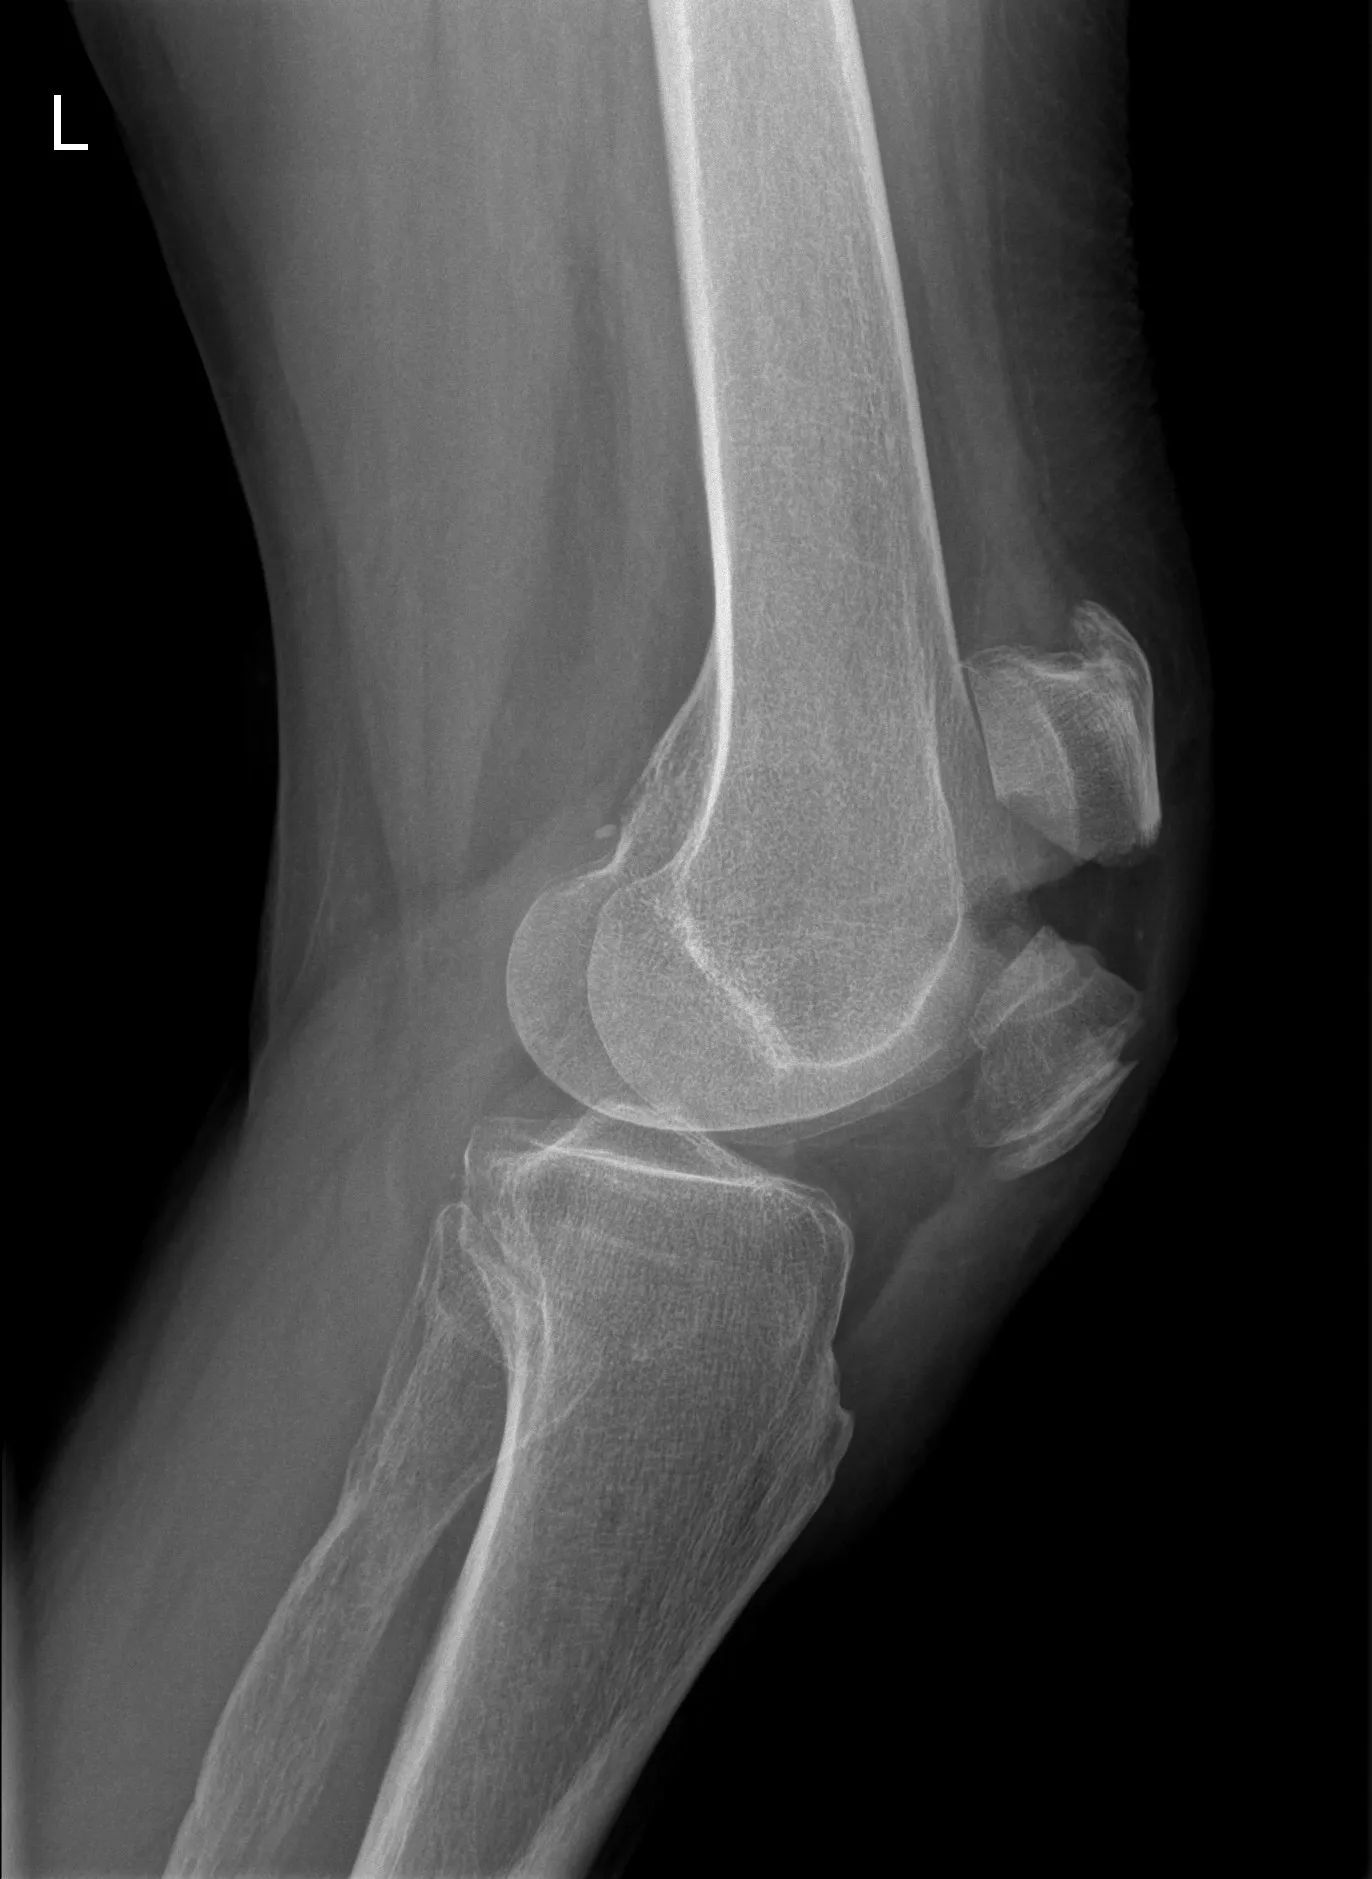

3. Beeldvorming: Een röntgenfoto van de knie wordt altijd gemaakt bij een vermoeden van patellafractuur. Meestal in voorachterwaartse en zijwaartse richting. Hierop is de breuklijn in de knieschijf zichtbaar en kan men zien of de fractuur verplaatst is. Als de fractuur niet goed zichtbaar is maar men vermoedt toch een barst, kan in enkele gevallen een CT-scan gedaan worden, maar doorgaans is de röntgenfoto voldoende.